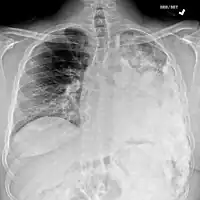

Metastatic osteosarcoma to the left chest